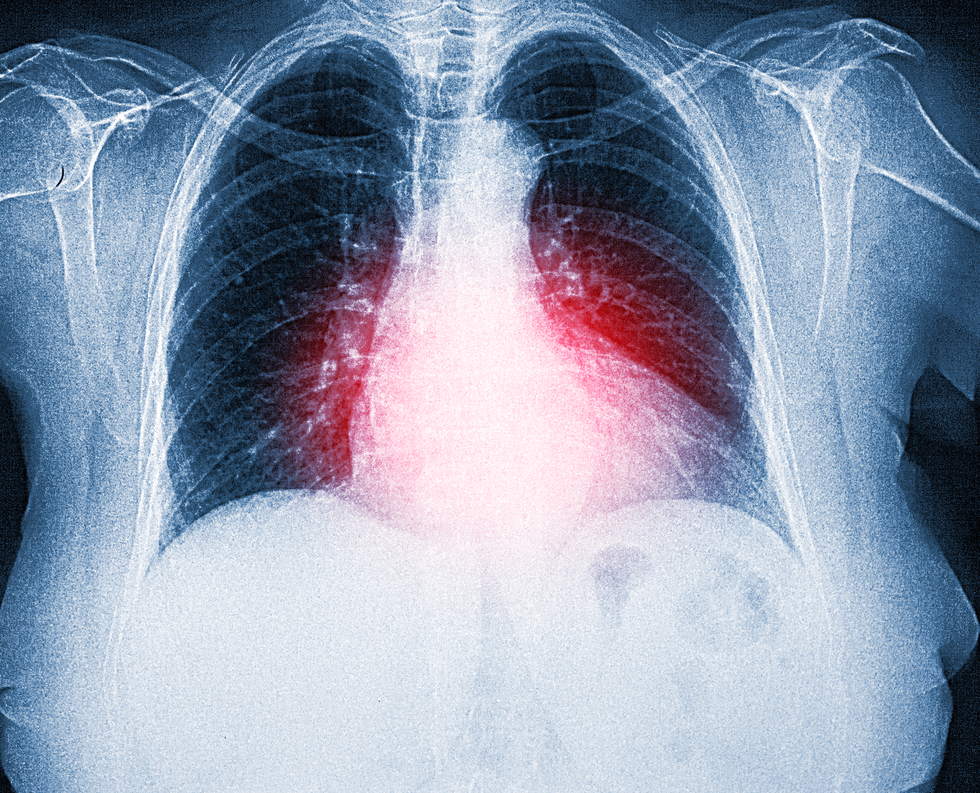

Many people who fall into the second category are now facing a second battle: lung damage.

Researchers from Brazil observed long-term functional abnormalities in the lungs of patients who had required intubation and were discharged from the hospital two years ago.

The São Paulo researchers also documented a return of pulmonary lesions after 24 months in some people who appeared to have fully recovered on being discharged.

Researchers from Brazil observed long-term functional abnormalities in the lungs of patients

|Getty Images